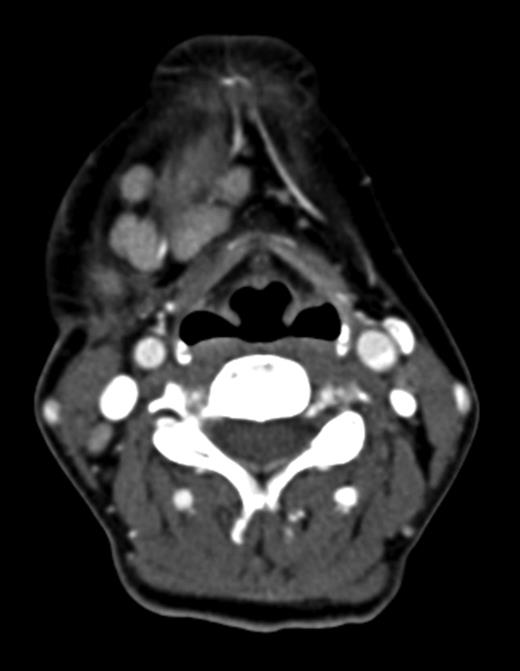

Computed tomography (CT) identified several enlarged submandibular lymph nodes (Figs 1 and 2).

Coronal CT (post contrast) showing enlarged right submandibular nodes.